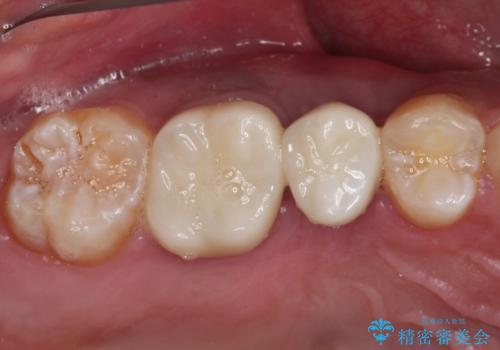

破折して抜歯が必要となった歯の後ろの歯は、根管治療が必要な状態であったので、根管治療を行い、矯正治療後にインプラント部の補綴治療と同時にセラミッククラウンを装着しました。

矯正治療以外に費用負担がかかることになりましたが、気になるところ全てを処置することができ、患者様には大変満足していただきました。